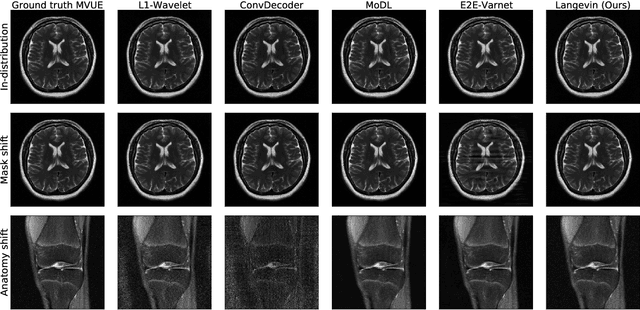

Abstract:The CSGM framework (Bora-Jalal-Price-Dimakis'17) has shown that deep generative priors can be powerful tools for solving inverse problems. However, to date this framework has been empirically successful only on certain datasets (for example, human faces and MNIST digits), and it is known to perform poorly on out-of-distribution samples. In this paper, we present the first successful application of the CSGM framework on clinical MRI data. We train a generative prior on brain scans from the fastMRI dataset, and show that posterior sampling via Langevin dynamics achieves high quality reconstructions. Furthermore, our experiments and theory show that posterior sampling is robust to changes in the ground-truth distribution and measurement process. Our code and models are available at: \url{https://github.com/utcsilab/csgm-mri-langevin}.